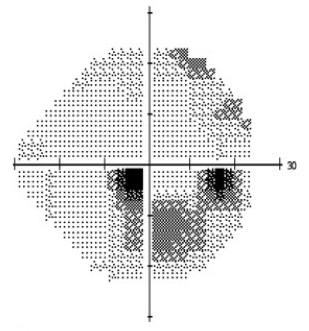

Optic disc imaging

Due to the irreversible loss of vision due to glaucomatous damage, early detection and treatment is paramount. Visual field testing is useful in early detection but may miss early, pre-perimetric disease, as substantial retinal nerve fiber layer may be lost before functional field defects are noted. Therefore, optic disc imaging is an important and objective structural assessment of the optic nerve health. For several decades, the gold standard for detecting disease and monitoring changes in the optic nerve head has been stereo disc photography (Figure 3 a,b). In recent years, scanning laser ophthalmoscopy and optical coherence tomography (OCT) is gaining popularity as another means of detecting pathologic thinning of neural tissue and monitoring progression. (See main article on eyewiki.aao.org/Optic_Nerve_and_Retinal_Nerve_Fiber_Imaging ) Moreover, with the introduction of Artificial Intelligence (AI), OCT interpretation continues to become more prevalent when classifying an eye as either a glaucoma suspect or early NTG. This was demonstrated in a recent study where a deep-learning algorithm was developed to discriminate between the aforementioned diagnoses by using the parameter of Bruch’s membrane opening — minimum rim width, peripapillary retinal nerve fiber layer (RNFL) thickness and color classification of RNFL — achieving an area under the curve of 0.966. Ultimately, these advances continue to improve the diagnostic specificity associated with either NTG or POAG.[53]

Figure 3: Optic disc photographs of a) right and b) left eye in a patient with normal tension glaucoma. Note the focal superotemporal thinning and associated dropout of the retinal nerve fiber layer. The corresponding visual field defects are seen in Figure 2.